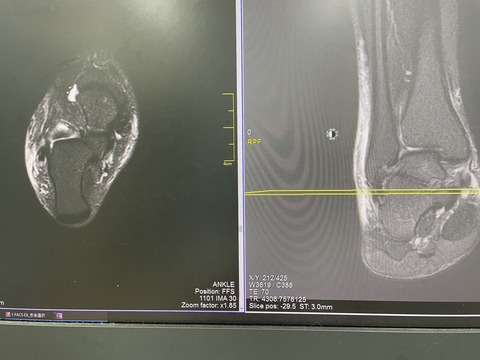

練習中に足の怪我をしました、